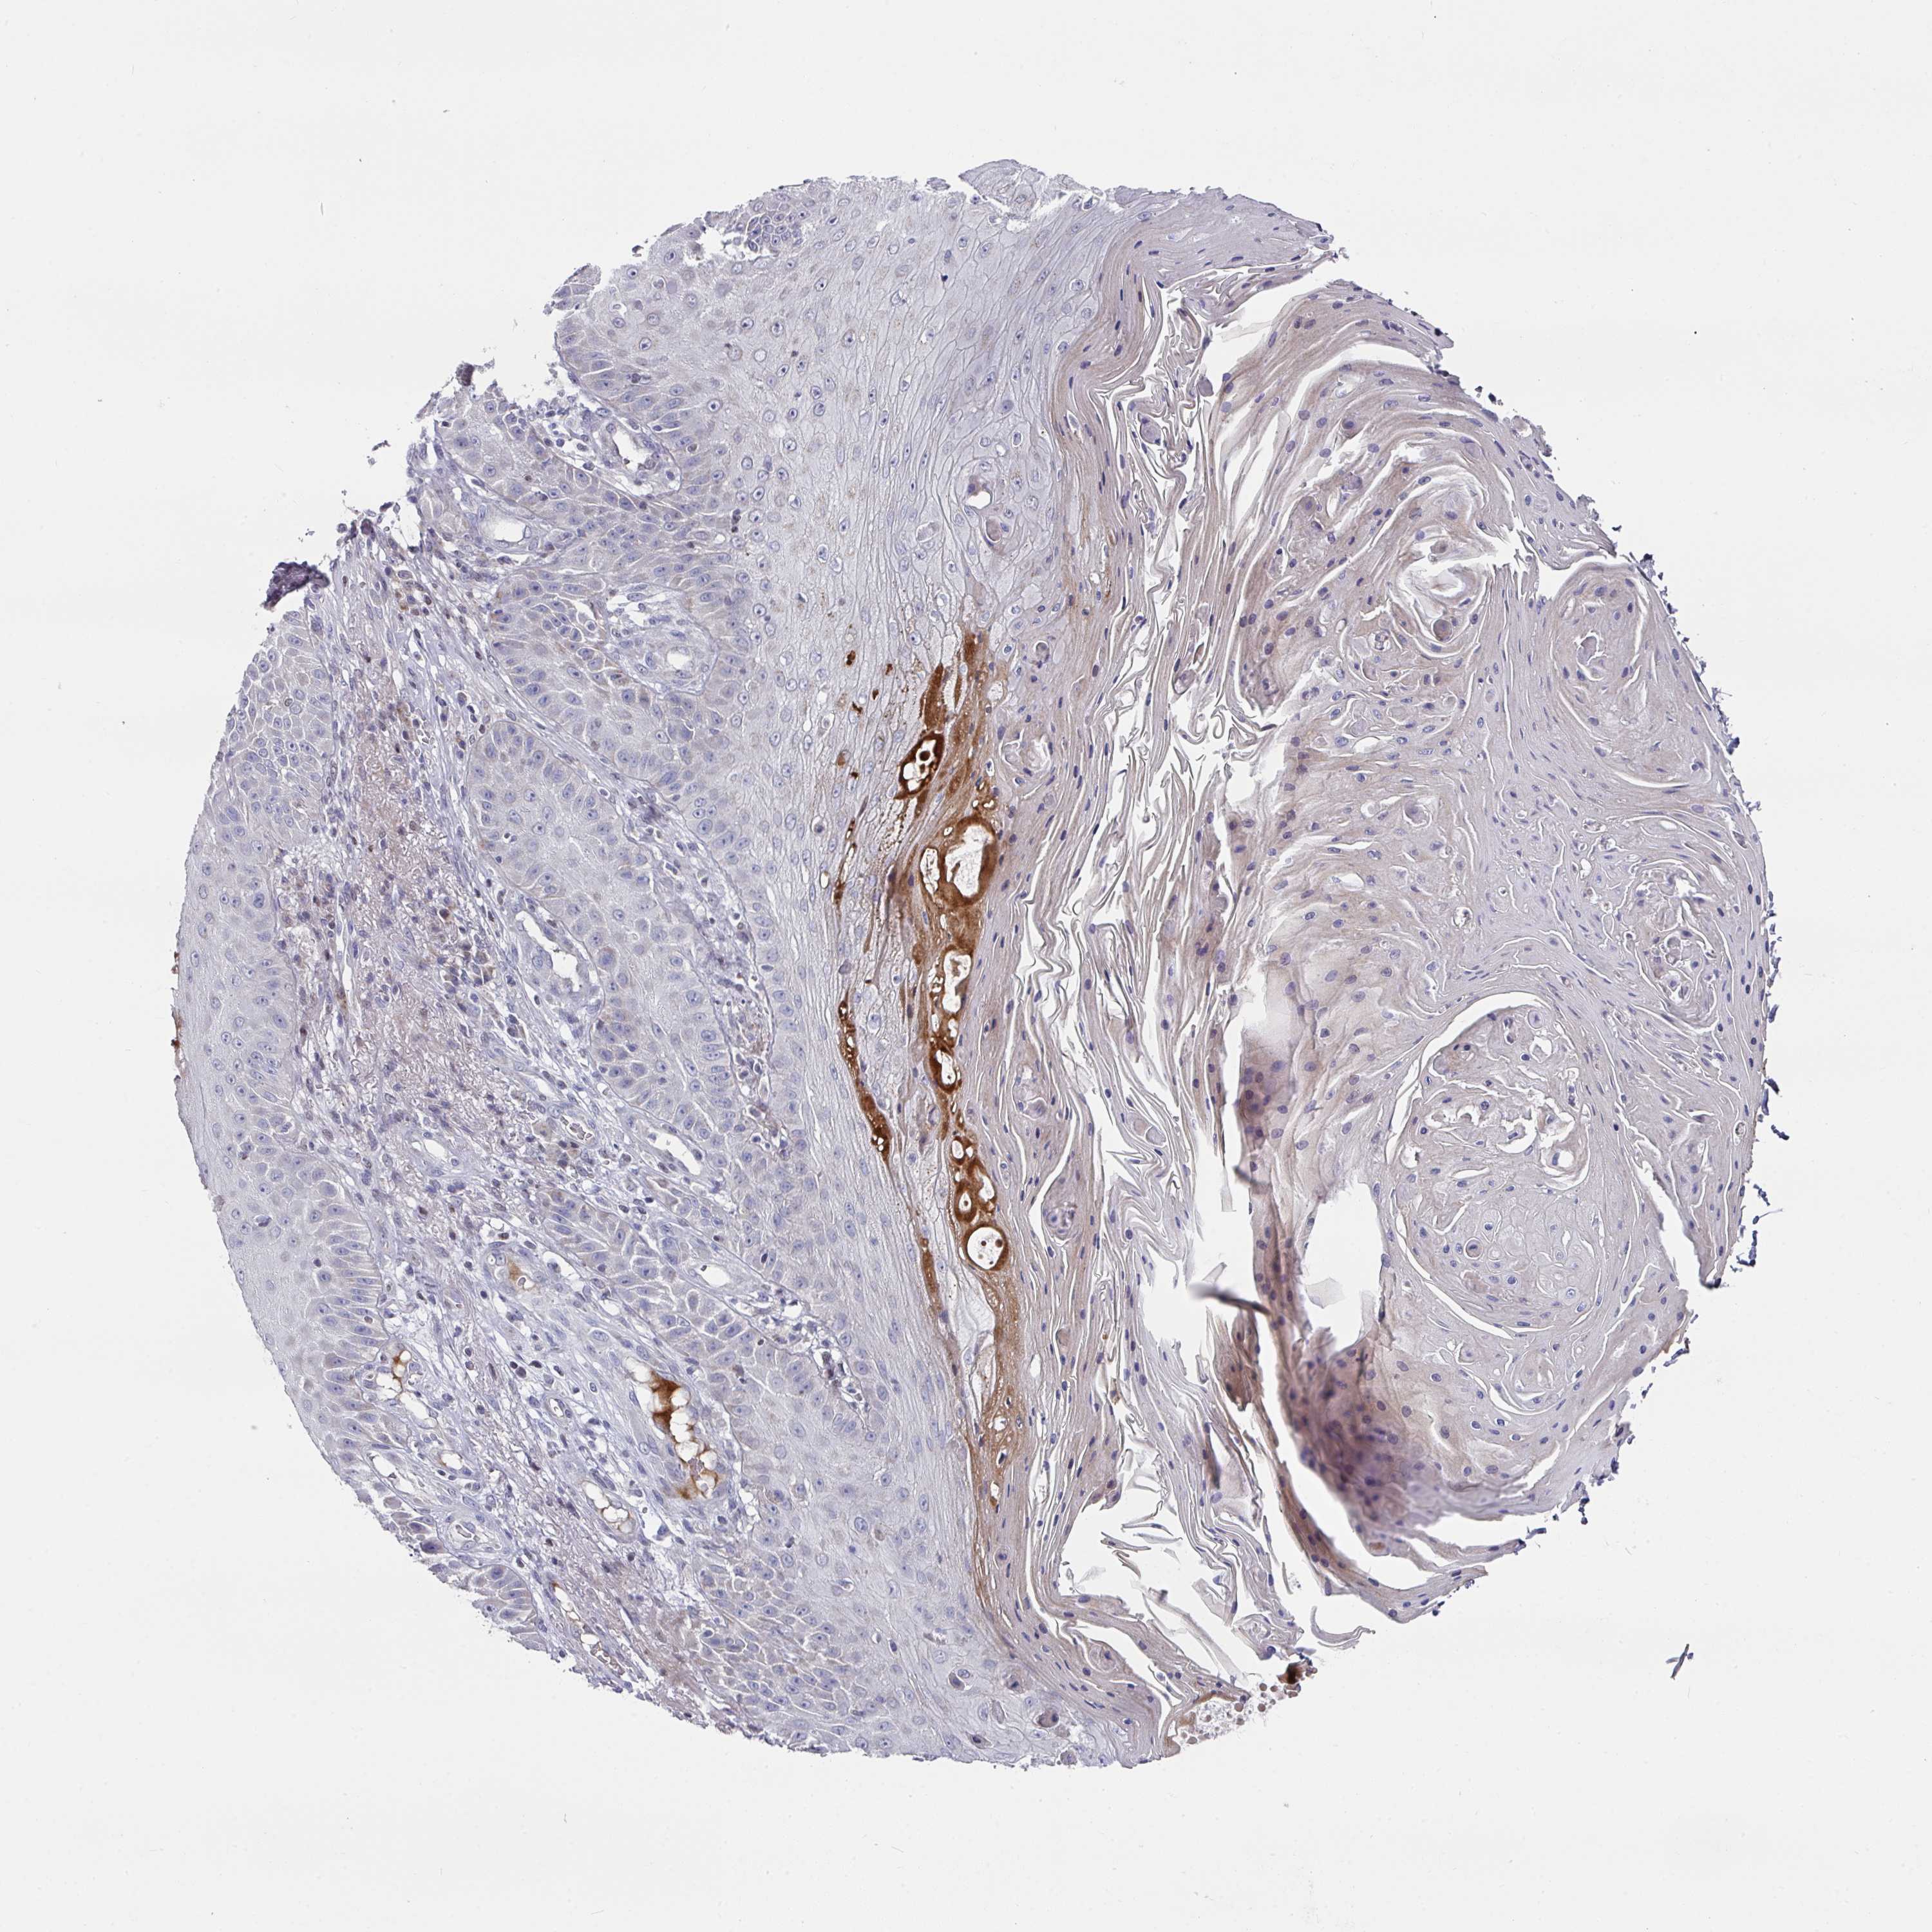

SKIN CANCER - Protein expressioni

A mouse-over function shows sample information and annotation data. Click on an image to view it in a full screen mode. Samples can be filtered based on level of antibody staining by selecting one or several of the following categories: high, medium, low and not detected. The assay and annotation is described here.

Antibody stainingi

Antibody staining in the annotated cell types in the current human tissue is reported as not detected, low, medium, or high, based on conventional immunohistochemistry profiling in selected tissues. This score is based on the combination of the staining intensity and fraction of stained cells.

Each image is clickable and will lead to virtual microscopy that enables deeper exploration of all samples and also displays staining intensity scores, fraction scores and subcellular localization as well as patient and tissue information for each sample.

Antibody HPA056480

Staining

High

Strong

>75%

Nuclear

Squamous cell carcinoma, NOS